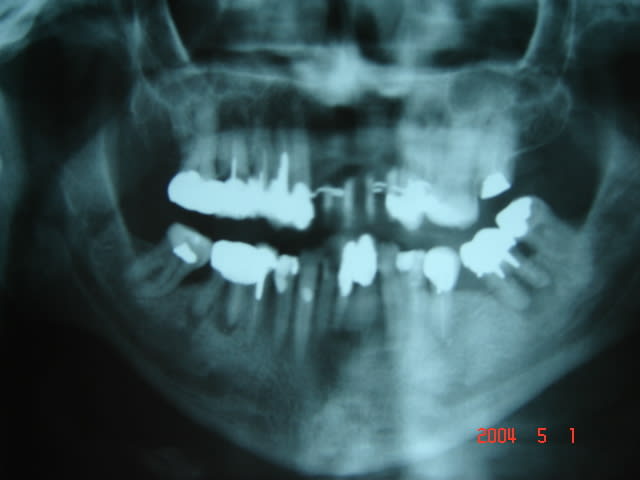

09/01/2006 à 15h28

et le scanner .

Imagerie ghomrani 002 mjfu7r - Eugenol